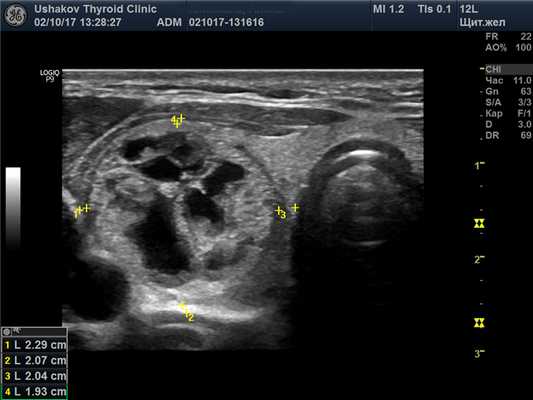

Структура паренхимы долей щитовидной железы неоднородная – узловая, вне узлов преобладает изоэхогенность.

В правой доле щитовидной железы в центрально-каудальной части почти до её краев (в поперечной проекции) расположен овоидоподобной формы узел 22,9х20,7х33,1 мм (7,4 мл), окруженный по всему периметру чёткой гипоэхогенной границей-контуром, значительно неоднородный за счет множественных анэхогенных (жидкостных) участков (около 70% от объёма узла), преимущественно с чёткими границами в виде узких перегородок с изо- и гиперэхогенной (фиброзной) тканью и изоэхогенной тканью по периметру узла; при ЭДК заметно примыкание к узлу с кранио- и каудальной сторон магистральных сосудов, и умеренный кровоток по части периметра и мало интенсивный внутри узла (в перегородках); при эластографии SR 2,8 (3,3 - в обл. некоторых перегородок). Вне узла ткань изоэхогенная, почти однородная; в краниальном полюсе 21,2х15х15,1 мм (2,3 мл), а также медиально. В режиме ЦДК и ЭДК кровообращение в этой ткани в малой степени усилено.

Рис. 27.5. Пример 1. (правая доля, поперечная проекция).

Латерально и вентрально за узлом – лишь тонкий слой ткани. Медиально заметна значимая часть внеузловой ткани. Узел в поперечной проекции подобен кругу. Чёткий гипоэхогенный контур по всему периметру узла.

Рис. 27.7. Пример 1. (правая доля, продольная проекция).

Структура узла представлена крупными сегментами, в центре которых – кистозные участки, почти повторяющие форму сегментов узла. Жидкостная (анэхогенная) часть узла преобладает над тканевой.

Узловой процесс. Узел в правой доле является крупным, т.к. его объём превышает 4 мл. Большая часть этого объёма состоит из жидкости. Поэтому важно указать величину жидкой части внутри узла.

Поскольку не всегда возможно вычислить объём жидкости в узле точно, то уместно сообщить в описании протокола ориентировочно выявленный вами процент жидкой части узла. Не забывайте применять слова «приблизительности» при таком выражении данных (почти, около и пр.).

Все признаки узла (в режимах В, ЭДК, ЦДК) в этом примере указывают на доброкачественный процесс. Форма узла приближена к правильной, стремится повторить форму доли. Узел имеет чёткую границу и гипоэхогенный (сосудистый) контур по всему периметру, распределение сосудов и. закономерные изменения внутри. Доброкачественность остаточной ткани подтверждается и при эластографии (SR 2,8).

Обратите внимание на сегментарное устройство ткани узла. Весь узел состоит из средней величины сегментов, внутри которых за счёт деструкции ткань распалась и накопилась жидкость. Это естественное стадийное изменение. Величина и распространённость деструкции в узле (почти все его сегменты имеют признаки значительного разрушения (рис. 27.11)) указывают на стадию значительного истощения.